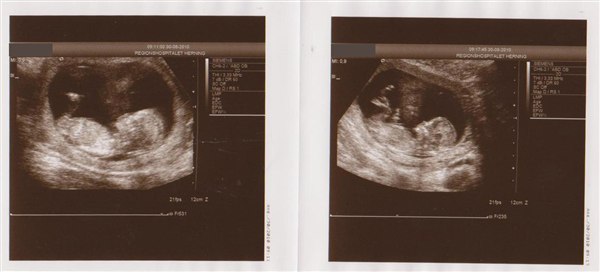

Jeg var til min scanning 13+3 (eller egentlig 13+2 men blev rykket en dag

) Og vi skal til MD scanning den 12 okt så DET glæder vi os til for det var da det største jeg har oplevet, at se min baby!